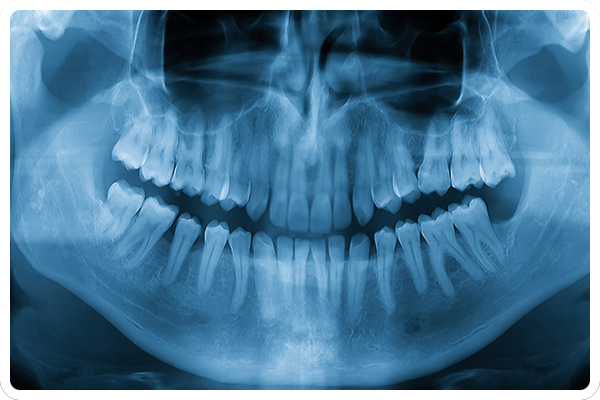

一般歯科について

お口の痛みや違和感に

幅広く対応する一般歯科診療

むし歯が痛い、歯ぐきが腫れてきた、噛むと違和感があるなど、お口の不調に気づいたときは、できるだけ早めの受診をおすすめします。当院では、急な症状への対応はもちろん、再発を防ぐためのケアや生活習慣へのアドバイスにも力を入れています。一人ひとりの状態を丁寧に診査したうえで、わかりやすくご説明しながら治療を進めていきますので初めてのかたも安心してご相談ください。

精度を上げるための設備

歯科用CT

根の形や曲がり具合、病巣の有無を立体的に把握できる歯科用CTを使用し、正確な診断と治療計画の立案につなげています。